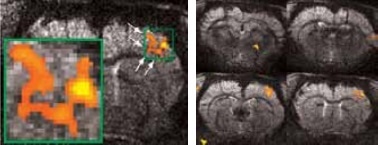

High resolution BOLD activation at 11.7 Tesla using the four-element array coil with a resolution of 75 x 75 x 1000 μm3 for detection of (left) sub-structures within S1, and activation within other regions along the neuronal pathway: S2 and thalamus

Figure 3. High resolution BOLD activation at 11.7 Tesla using the four-element array coil with a resolution of 75 x 75 x 1000 μm3 for detection of (left) sub-structures within S1, and activation within other regions along the neuronal pathway: S2 and thalamus. Image Credit: Bruker BioSpin Group

Matrices up to 256 x 256 were obtained with a four-element array coil, resulting in 75 x 75 x 1000 μm3 resolution. The activation becomes more resolved at this high resolution and allows the detection of sub-structures and shape in thalamus areas S1 and S2, as shown in Figure 3.

Typically, BOLD contrast increases with higher field strength as a result of increased sensitivity. Owing to reduced effects of partial volume, the BOLD sensitivity is further enhanced by increased spatial resolution. When using the quadrature coil, it was observed that BOLD contrast increased from 1.5% at a resolution of 400 x 400 x 1000 μm3 to as high as 4% at 150 x 150 x 1000 μm3 at 11.7 Tesla.

Sub-structures can be easily detected at higher resolutions. At such resolutions, BOLD contrast reduced as a result of reduced SNR. However, in these analyses, an instant increase of BOLD contrast with field strength, seen up to 7.0 Tesla (Figure 4). which was no longer observed.

This is because of decreasing intravascular contributions as well as decreasing extravascular contributions from arterioles and venules. Short T2 values of blood explain these changes at such high field[3]. Yet, higher S/N is provided by increasing field strength, and when this S/N is invested into higher spatial resolution, it provides access to finer details of sub-structures and at the same time boosts the BOLD amplitude (due to less “dilution” by partial volume effect).